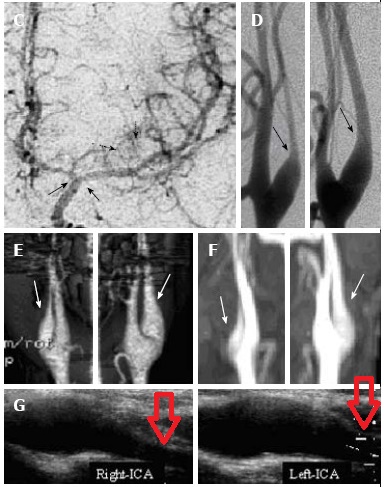

甲状腺機能亢進症/バセドウ病に合併する可逆的頸部内頸動脈狭窄は、類もやもや病と同じく

- 大部分は女性

- 若年発症

- 原因として

①交感神経亢進状態で血管収縮(Gen Pharmacol. 2000 Jun;34(6):429-34.)②循環血液量増大・心拍出量増大・頻脈による血管内皮障害(Biomed Pharmacother. 2002 Jul;56(5):241-6.)(Sci Rep. 2020 Apr 24;10(1):6992.)③共通の自己免疫(Stroke. 2011 Apr;42(4):1138-9.)④遺伝性(Neurol Med Chir (Tokyo).2010;50(8):668-74.)(Jpn J Stroke 34: 82–88, 2012)

(A case of reversible stenosis in the cervical internal carotid artery causing cerebral infarction associated with Basedow disease. Jpn J Stroke 36: 51–53, 2014)